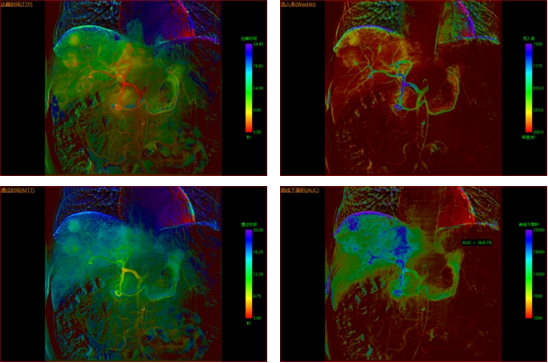

比如目前常见的肝癌核心术式之一TACE化疗栓塞术治疗,其疗效精准性与安全性长期依赖临床经验判断,而今通过多模态影像评估的智能模块应用,结合介入造影灌注影像与临床数据就可量化分析栓塞前后肿瘤体积的变化、血供变化及组织灌注情况,辅助疗效评估和肝功能预测,给出临床最佳栓塞剂量推荐,显著提升TACE疗效与安全性。